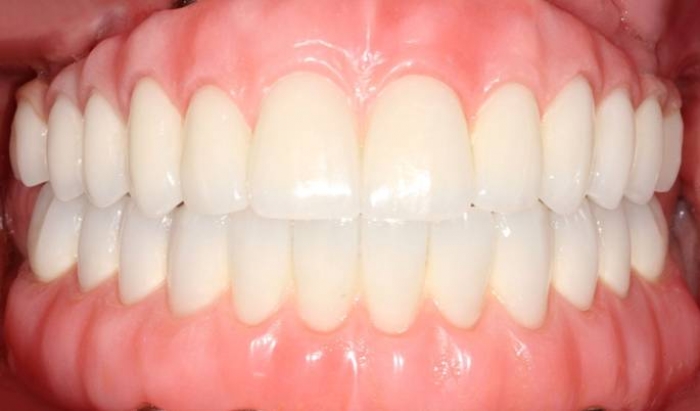

Próteses fixas em porcelana sobre implantes - Clínica Cliniface

Próteses fixas em porcelana sobre implantes

Sorriso final do caso terminado em Dezembro de 2011 - Clínica Cliniface

Sorriso final do caso terminado em Dezembro de 2011